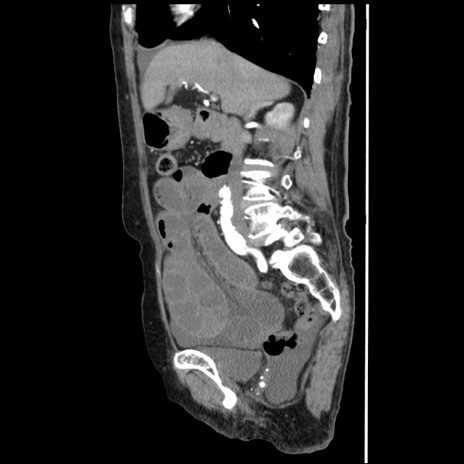

冠状断像